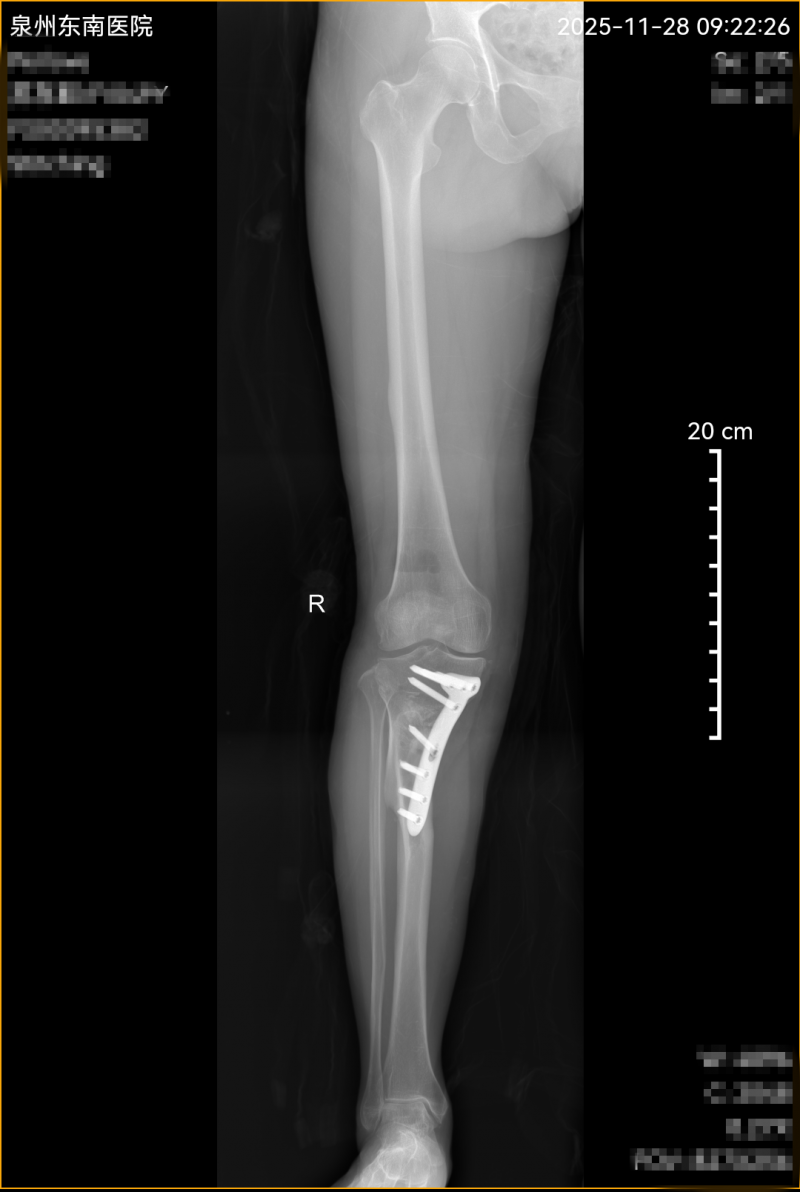

转机出现在泉州东南医院骨科。张阿姨打听到,该院副院长姜雪松带领的骨科团队在“保膝”治疗方面经验丰富,特意从安溪老家赶来求诊。检查结果印证了病情的复杂:X光片清晰显示右膝关节严重内翻畸形,属于典型的“下肢力线不正”。

经过严谨评估,姜副院长给出了希望的答案:“她的膝关节内侧软骨虽然磨损,但外侧相对完好,仍有修复空间。胫骨高位截骨术(HTO)是最佳选择——不用置换关节,只需精准矫正‘歪掉’的力线,让膝盖重新‘受力均匀’,就能保住原有关节!”这一方案,让张阿姨悬着的心终于放下。

姜副院长形象地比喻HTO手术:“这就像给膝盖‘调重心’、‘扶正桌子腿’。”具体而言,通过在胫骨近端(高位)进行精确的双平面截骨,医生能像“调整门框”一样矫正畸形角度,将原本偏向内侧的巨大压力合理分配到整个关节面。这样不仅能有效矫正“罗圈腿”,还能为不堪重负的内侧软骨“减负”,创造自我修复的条件。